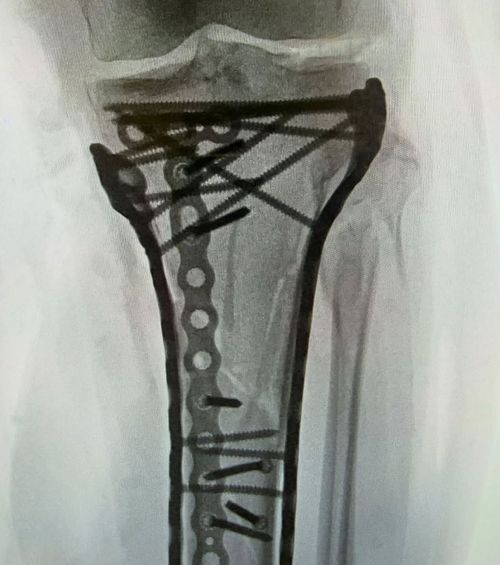

Așa arată gamba stângă a lui Vonn după accidentarea de Jocurile Olimpice și operațiile suferite. Foto: Instagram

Un mesaj pentru fani, pe Instagram și X. „Ultima mea operație a decurs bine. A durat puțin peste șase ore. Așa cum vedeți, a fost nevoie de multe plăcuțe și șuruburi pentru a pune totul la loc.

M-am recuperat, dar durerea a fost greu de suportat. Din cauza gravității traumei, am suferit după operație. Sper să ies în curând din spital”, a scris ea.

Le-a arătat și radiografia gambei stângi. Și toate lucrurile metalice cu care i-a fost fixată tibia.

Într-o altă postare, pe X, a comentat cu umor lângă radiografie: „Acum sunt cu adevărat bionică”.